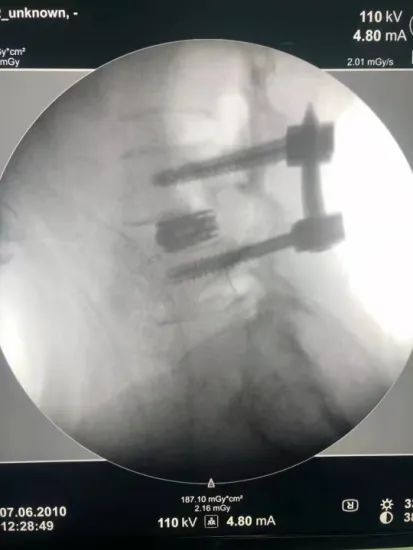

第二天一早,陈建军主任到会泽县中医医院骨伤科进行查房及手术指导。该手术患者为一例长期受腰腿疼痛的老年患者,诊断为“腰椎滑脱(腰4二度)”。陈建军主任为患者行的术式为“全内镜下腰椎微创减压椎间融合技术(PE-TLIF)”,该手术具有创伤小、出血少、费用低、恢复快、并发症少等优势。

手术图示:在腰部做大小如“纽扣”大小的五个小眼,即可完成手术

手术后影像资料